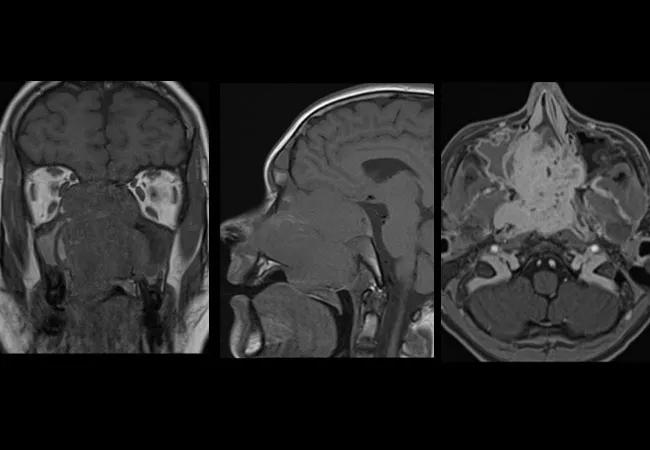

Left. Coronal T1 MRI shows a very large nasal mass abutting the internal carotid arteries and right orbital apex. Center. Sagittal view shows the erosion of the clivus the floor of the anterior cranial fossa cribriform. Right. Axial T1 shows the involvement of the right pterygoid plates.

After inpatient admission, the patient had a T1 MRI (above) which revealed a very large nasal mass abutting the internal carotid arteries and right orbital apex, erosion of the clivus on the floor of the anterior cranial fossa cribiform and involvement of the right pterygoid plates. Unfortunately, given the duration of vision loss in the right eye, return of vision was not possible.